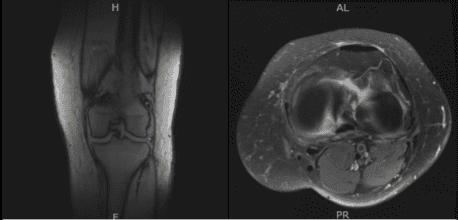

Se realizó una resonancia magnética para el diagnóstico. Hay un derrame articular de tamaño moderado e inflamación capsular. Los ligamentos cruzados anterior y posterior están intactos. Existe una compleja desgarro del cuerpo y del cuerno posterior del menisco medial. El menisco lateral está intacto.

El tendón del cuádriceps y el tendón rotuliano están intactos. Los ligamentos colaterales medial y lateral están intactos. Hay condromalacia patelofemoral moderada con erosión parcial de 15 mm que afecta a la faceta medial de la rótula. No se identificó ningún defecto subcondral ni fractura. Hay un encondroma de 10 mm en la metáfisis distal del fémur medialmente.

No se identificó ningún defecto o fractura osteocondral. En el resultado de la resonancia, se detectó una compleja desgarro del cuerpo y del cuerno posterior del menisco medial. Condromalacia patelofemoral moderada asociada a derrame articular de tamaño moderado e inflamación capsular.

MRI-3T Rodilla Izquierda sin contraste